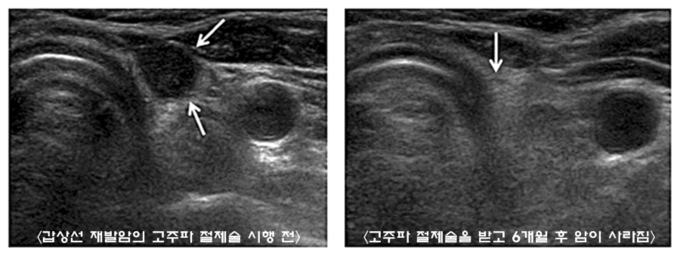

갑상선 재발암의 고주파절제술은 국소마취만 한 상태에서 초음파를 보면서 고주파 전극을 재발암에 정확하게 삽입한 후 고주파 전류를 통하게 되면 섭씨 100도 정도의 마찰열이 발생하게 되는데 이 마찰열로 종양 세포를 없애는 방법이다.

갑상선 고주파절제술의 세계적인 명성을 가진 백정환 교수팀은 이번 연구에서 목의 림프절에 갑상선암이 재발한 환자 39명에서 고주파절제술을 이용해 병변을 제거했다. 환자에 따라서 여러 개의 병변을 가지고 있어 치료한 총 종양의 개수는 61개였으며, 이들 종양은 치료 결과 종양의 크기가 평균 95% 감소했다.